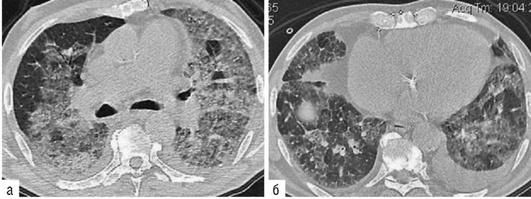

Лучевые методы исследования. Рентгенологическая картина при ЭТА зависит от стадии заболевания. В начальной фазе выявляются признаки отека интерстициальной ткани легких и распространенные мелкоочаговые затенения. При прогрессировании процесса формируются двусторонние изменения легочного рисунка по типу интерстициального фиброза, преимущественно в нижних отделах легких (рис. 2.28). В далеко зашедших случаях определяется мелко- и крупноячеистая деформация легочного рисунка. Описаны случаи, когда единственным рентгенологическим признаком болезни был односторонний плевральный выпот. Отсутствие каких-либо изменений на рентгенограммах отнюдь не исключает ЭТА. Так, при бериллиозе у 23-59% больных может выявляться умеренно выраженная двусторонняя лимфоаденопатия, а в ряде случаев - рентгенотрицательная форма бериллиоза (Dweik R.A., 2015). У 30% из 71 больных ЭТА, наблюдавшихся нами в клинике пульмонологии, в момент обследования изменений на рентгенограммах не было (Орлова Г.П., 2019). Группа больных ЭТА была обозначена условно как рентгенотрицательная группа. Уточнить диагноз помогает КТ легких, выявляющая интерстициальные изменения в легочной ткани по типу «матового стекла», усиление и деформацию легочного и сосудистого рисунка (рис. 2.29), фиброзные изменения тяжистого и звездчатого типов, на поздних стадиях - «сотовое легкое». ВРКТ выявляет «матовое стекло» и другие изменения в легочной паренхиме, которые не видны при обычном рентгенологическом исследовании. Но даже ВРКТ не всегда выявляет изменения в легочной ткани. Так, в 25% случаев гистологически подтвержденного хронического берил-лиоза легких ВРКТ была нормальной (Dweik R.A., 2013; Амосов В.И., Сперанская А.А., 2015; Amanullah S. et al., 2015).

Проведенное нами динамическое исследование КТ-паттернов у 42 больных ЭТА показало трансформацию отдельных типов интерстициальных пневмоний по мере прогрессирования патологического процесса в фиброзную НСИП или ОИП (рис. 2.30), что подтверждает объединительную концепцию интерстициальных пневмоний вне зависимости от этиологического фактора, которые являются не отдельными нозологическими формами, а стадиями течения фиброзирующего процесса в легких (Илькович М.М., Новикова Л.Н., 2018; Орлова Г.П. и др., 2019).